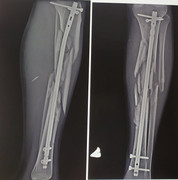

вот результат, я считаю весьма неплохой.

100% остеомиелит (гнойная хирургия), такое, только аппаратом Илизарова собирают.

нет.бардак с идеями писал(а): 25 сен 2022, 20:44 100% остеомиелит (гнойная хирургия), такое, только аппаратом Илизарова собирают.

современные препараты творят чудеса.

сначала жгут и в госпиталь.

в госпитале аппарат внешней фиксации и восстановление сосудов.

далее мск, интрамедуллярный остеосинтез.

снимок сделали на той неделе, в целом всё спокойно.

Спасибо, плавали, 30 лет назад, в ЦИТО, так собрали, а потом, в гнилухе Илизарова переделывали.alex_doctor писал(а): 25 сен 2022, 21:03нет.бардак с идеями писал(а): 25 сен 2022, 20:44 100% остеомиелит (гнойная хирургия), такое, только аппаратом Илизарова собирают.